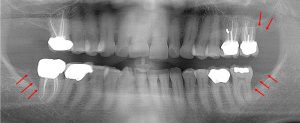

This 48 year old patient had all four 3rd molars extracted in his late 20’s. All four sites healed poorly and chronically infected bony defects remained. The upper right 2nd molar was extracted two years ago as a result of this chronic infection. The upper left 2nd molar must now be extracted because of a chronic periodontal infection moving around that tooth. Both lower molars are chronically infected and have a poor prognosis.